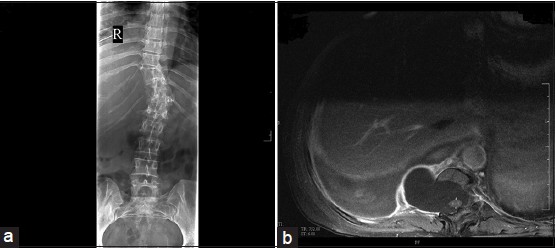

Figure 2: (a) Thoracolumbar plain radiograph; (b) chest computed tomography scan